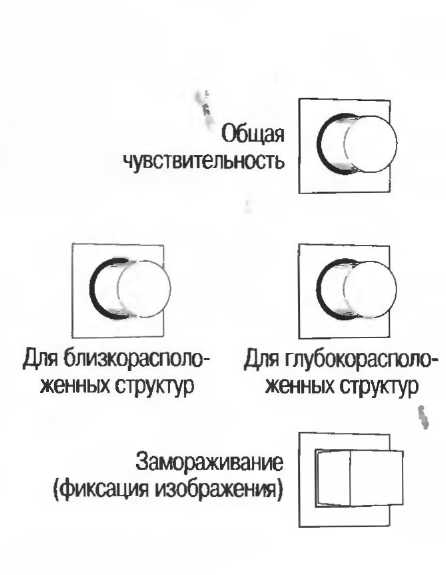

Контрольные устройства сканера

Сканер должен быть оборудован видеомонитором (телевизионным экраном), а для контроля качества изображения необходимо наличие:

1. Устройства регулировки общей чувствительности для изменения количества общей информации с видеоэкрана.

2. Устройства компенсации затухания ультразвука в поверхностных (близкорасположенных) и глубокорасположенных (отдаленных) структурах. Эти устройства называются устройствами регулировки чувствительности по глубине.

3. Устройства «замораживания» изображения для фиксации изображения на экране в течение необходимого времени.

Усиление отраженных ультразвуковых волн ультразвуковой системой. Отраженным сигналам, идущим от глубокорасположенных тканей, необходимо более интенсивное усиление, чем сигналам, поступающим от тканей, расположенных более поверхностно. В соответствии с этим ультразвуковой аппарат снабжен двумя системами контроля чувствительности прибора. Система изменения чувствительности при исследовании близкорасположенных тканей усиливает отраженные зхосигналы от структур, расположенных над точкой фокусировки ультразвукового луча, система изменения чувствительности при |

исследовании глубокорасположенных тканей усиливает эхосигналы, отраженные от структур, расположенных за точкой фокусировки ультразвукового луча. Эти системы существуют для получения одинаковой эхогенности одних и тех же тканей, но на различной глубине. |